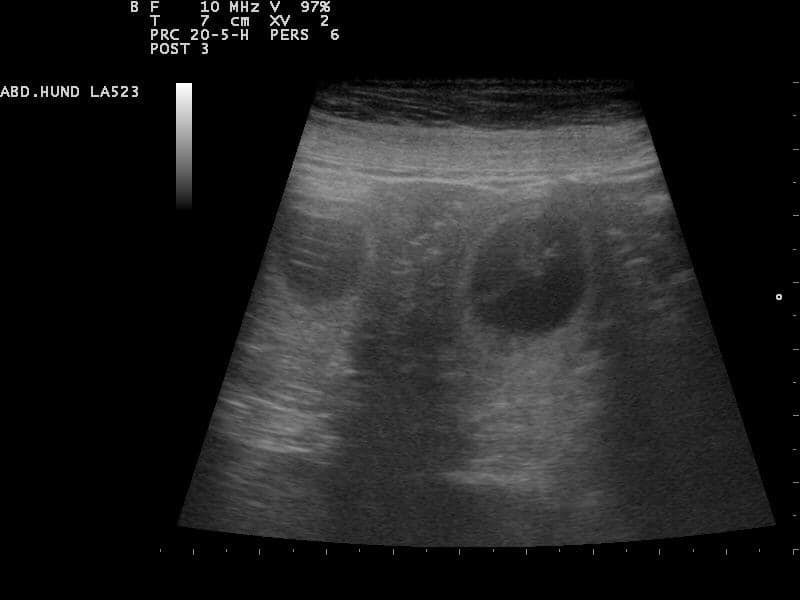

Die Entwicklung des Welpen im Leib der Hündin.